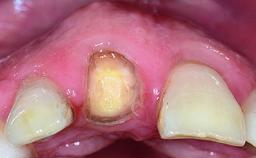

Replacement of a Missing Upper Left Central Incisor: Late Placement of an RC Bone Level Implant, CAD/CAM Zirconia Abutment

A healthy 37-year-old female patient was referred for a consultation on the replacement of missing tooth 21 with an implant-supported restoration. She stated that several years previously the tooth had been traumatically avulsed following a motor vehicle accident. The tooth was replaced with a three-unit fixed partial denture (FPD) immediately afterwards. Over time, she became disillusioned with the FPD and looked for a different option, including orthodontic therapy. She presented still in her orthodontic appliances, with the pontic sectioned free from the FPD but attached to the archwire. Her orthodontist felt that orthodontic treatment had been successfully completed, but nevertheless referred her before removing the appliances in case adjustments were necessary.

Bone Volume Deficient horizontally, allowing simultaneous augumentation